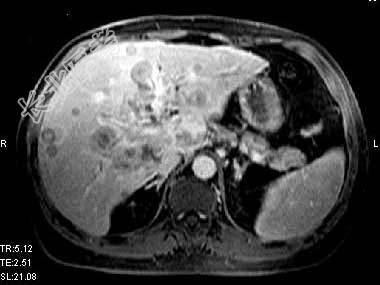

- 单项选择题根据所提供的图像,最可能的诊断是 ( )

A、肝转移癌

B、肝细胞癌

C、肝胆管细胞癌

D、肝血管瘤

E、以上都不是